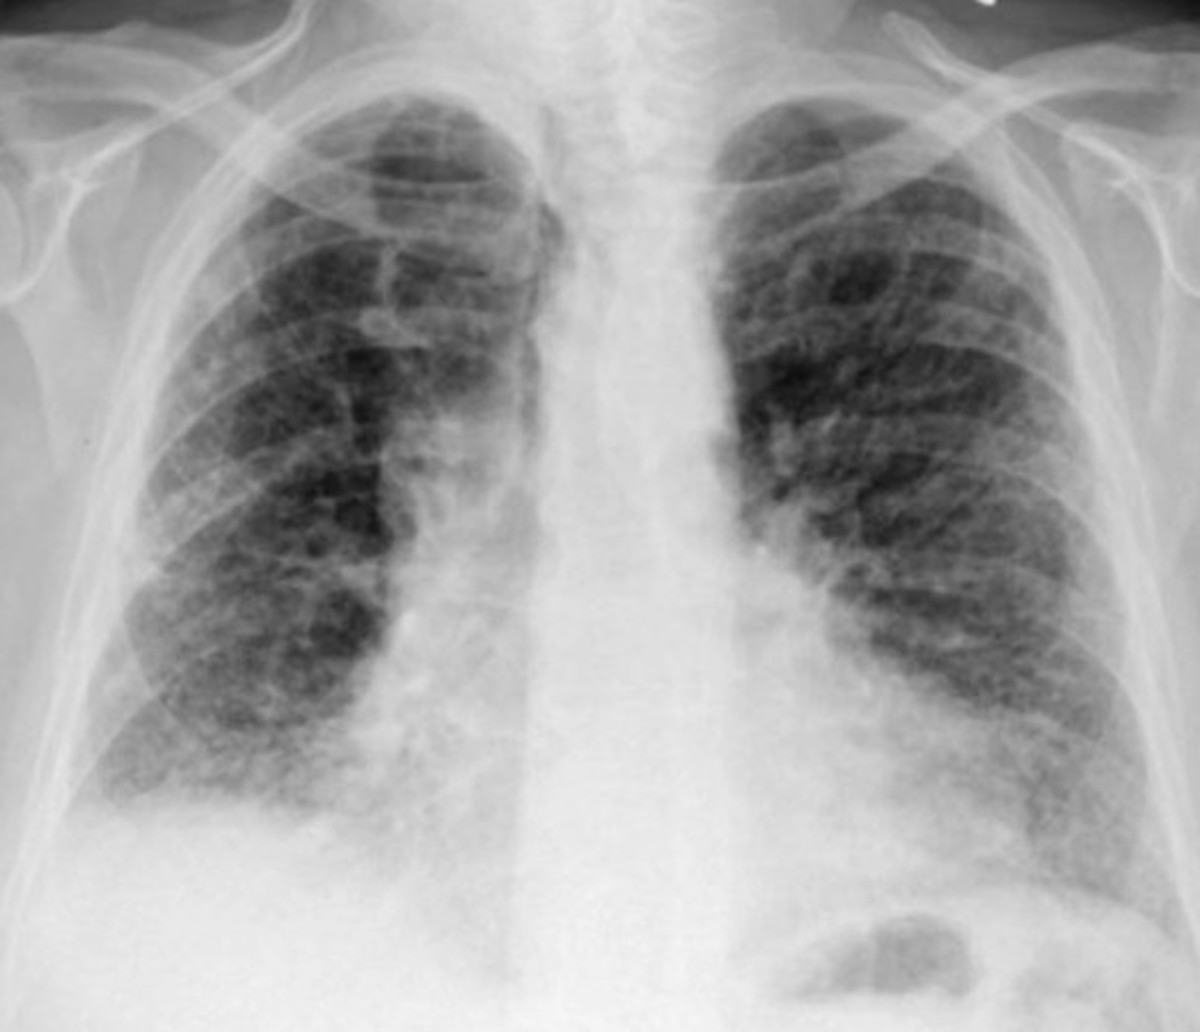

Disease Where Your Lungs Harden . Idiopathic pulmonary fibrosis (ipf) is a condition in which the lungs become scarred and breathing becomes increasingly difficult. Pulmonary fibrosis scars and thickens lung. This condition develops when that lung tissue. This makes it difficult to get oxygen into the. Pulmonary fibrosis is a group of serious lung diseases that affect the respiratory system. Interstitial lung disease refers to a group of about 100 chronic lung disorders characterized by inflammation and scarring that make it hard for. Learn more about the risk. Idiopathic pulmonary fibrosis (ipf) is a rare lung disease that causes scar tissue to grow inside your lungs. Avoid other things that can irritate your lungs. Idiopathic pulmonary fibrosis (ipf) is a serious chronic (long term) disease that affects the tissue surrounding the air sacs, or alveoli, in the lungs. Pulmonary fibrosis, or interstitial lung disease occurs when scar tissue builds up in your lungs, causing the lung tissue to thicken and harden. Breathing indoor pollutants, such as fumes from heating fuel or chemicals, can irritate.